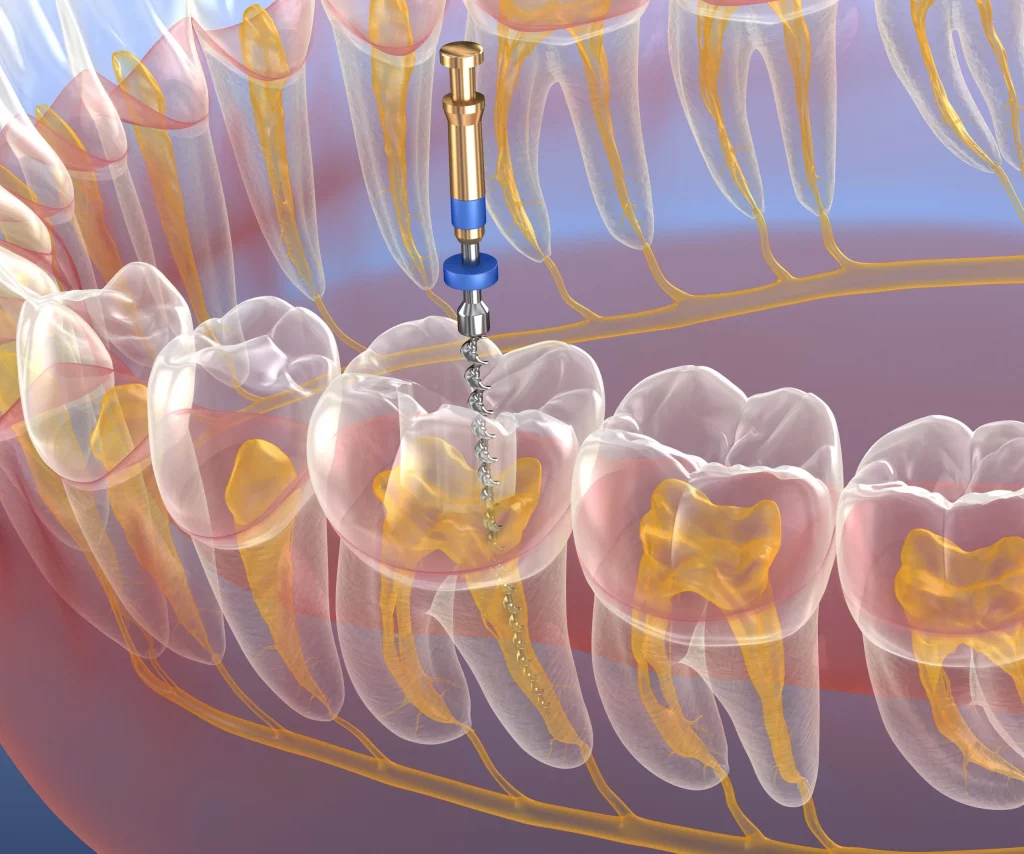

Endodoncia (salvar tu diente)

Cuando la caries o un traumatismo llega al nervio, la endodoncia permite eliminar el dolor y conservar el diente, evitando en muchos casos la extracción. Planificamos con cuidado para que el resultado sea estable y duradero.

¿Qué es una endodoncia y para qué sirve?

La endodoncia (tratamiento de conductos) elimina la infección o inflamación del nervio para salvar el diente y quitar el dolor. Es una alternativa para conservar piezas que, de otro modo, podrían perderse.

¿Duele una endodoncia?

Se realiza con anestesia, por lo que el procedimiento es cómodo y controlado. Tras el tratamiento puede haber molestias leves, pero suelen ser temporales y te indicamos pautas claras para recuperarte bien.